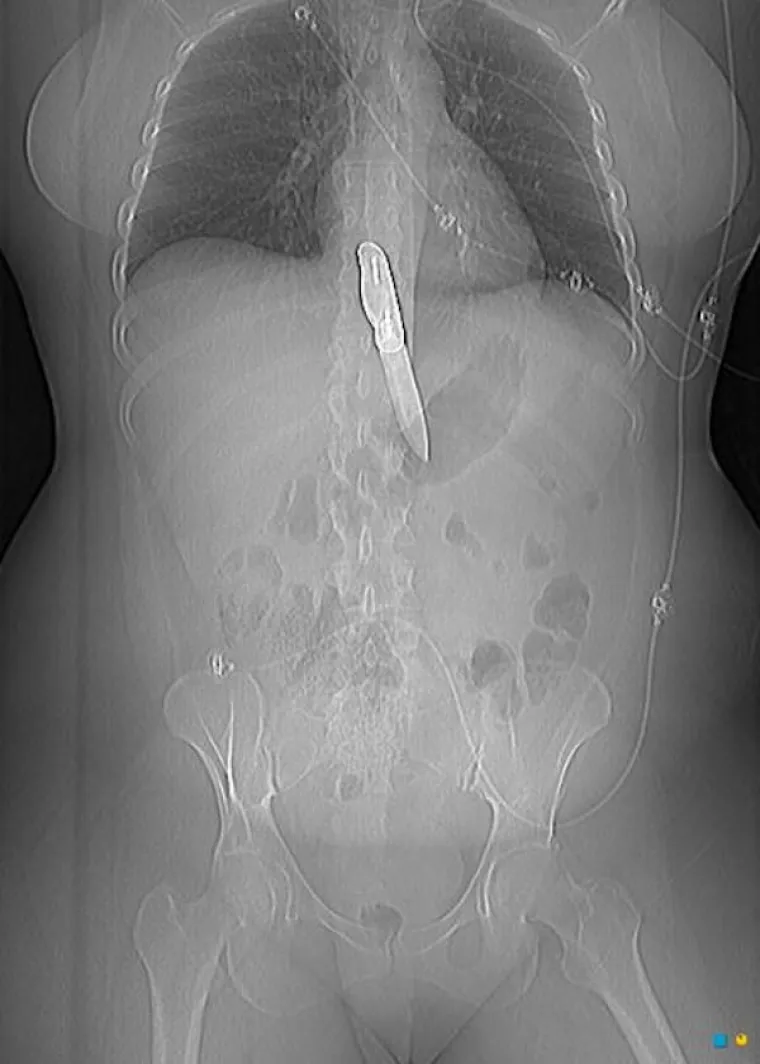

LJUDI SU ČAROBNO SPREMIŠTE, U NJIH STANE BAŠ SVE: Nevjerojatne snimke pokazuju što su sve uspjeli ugurati u sebe